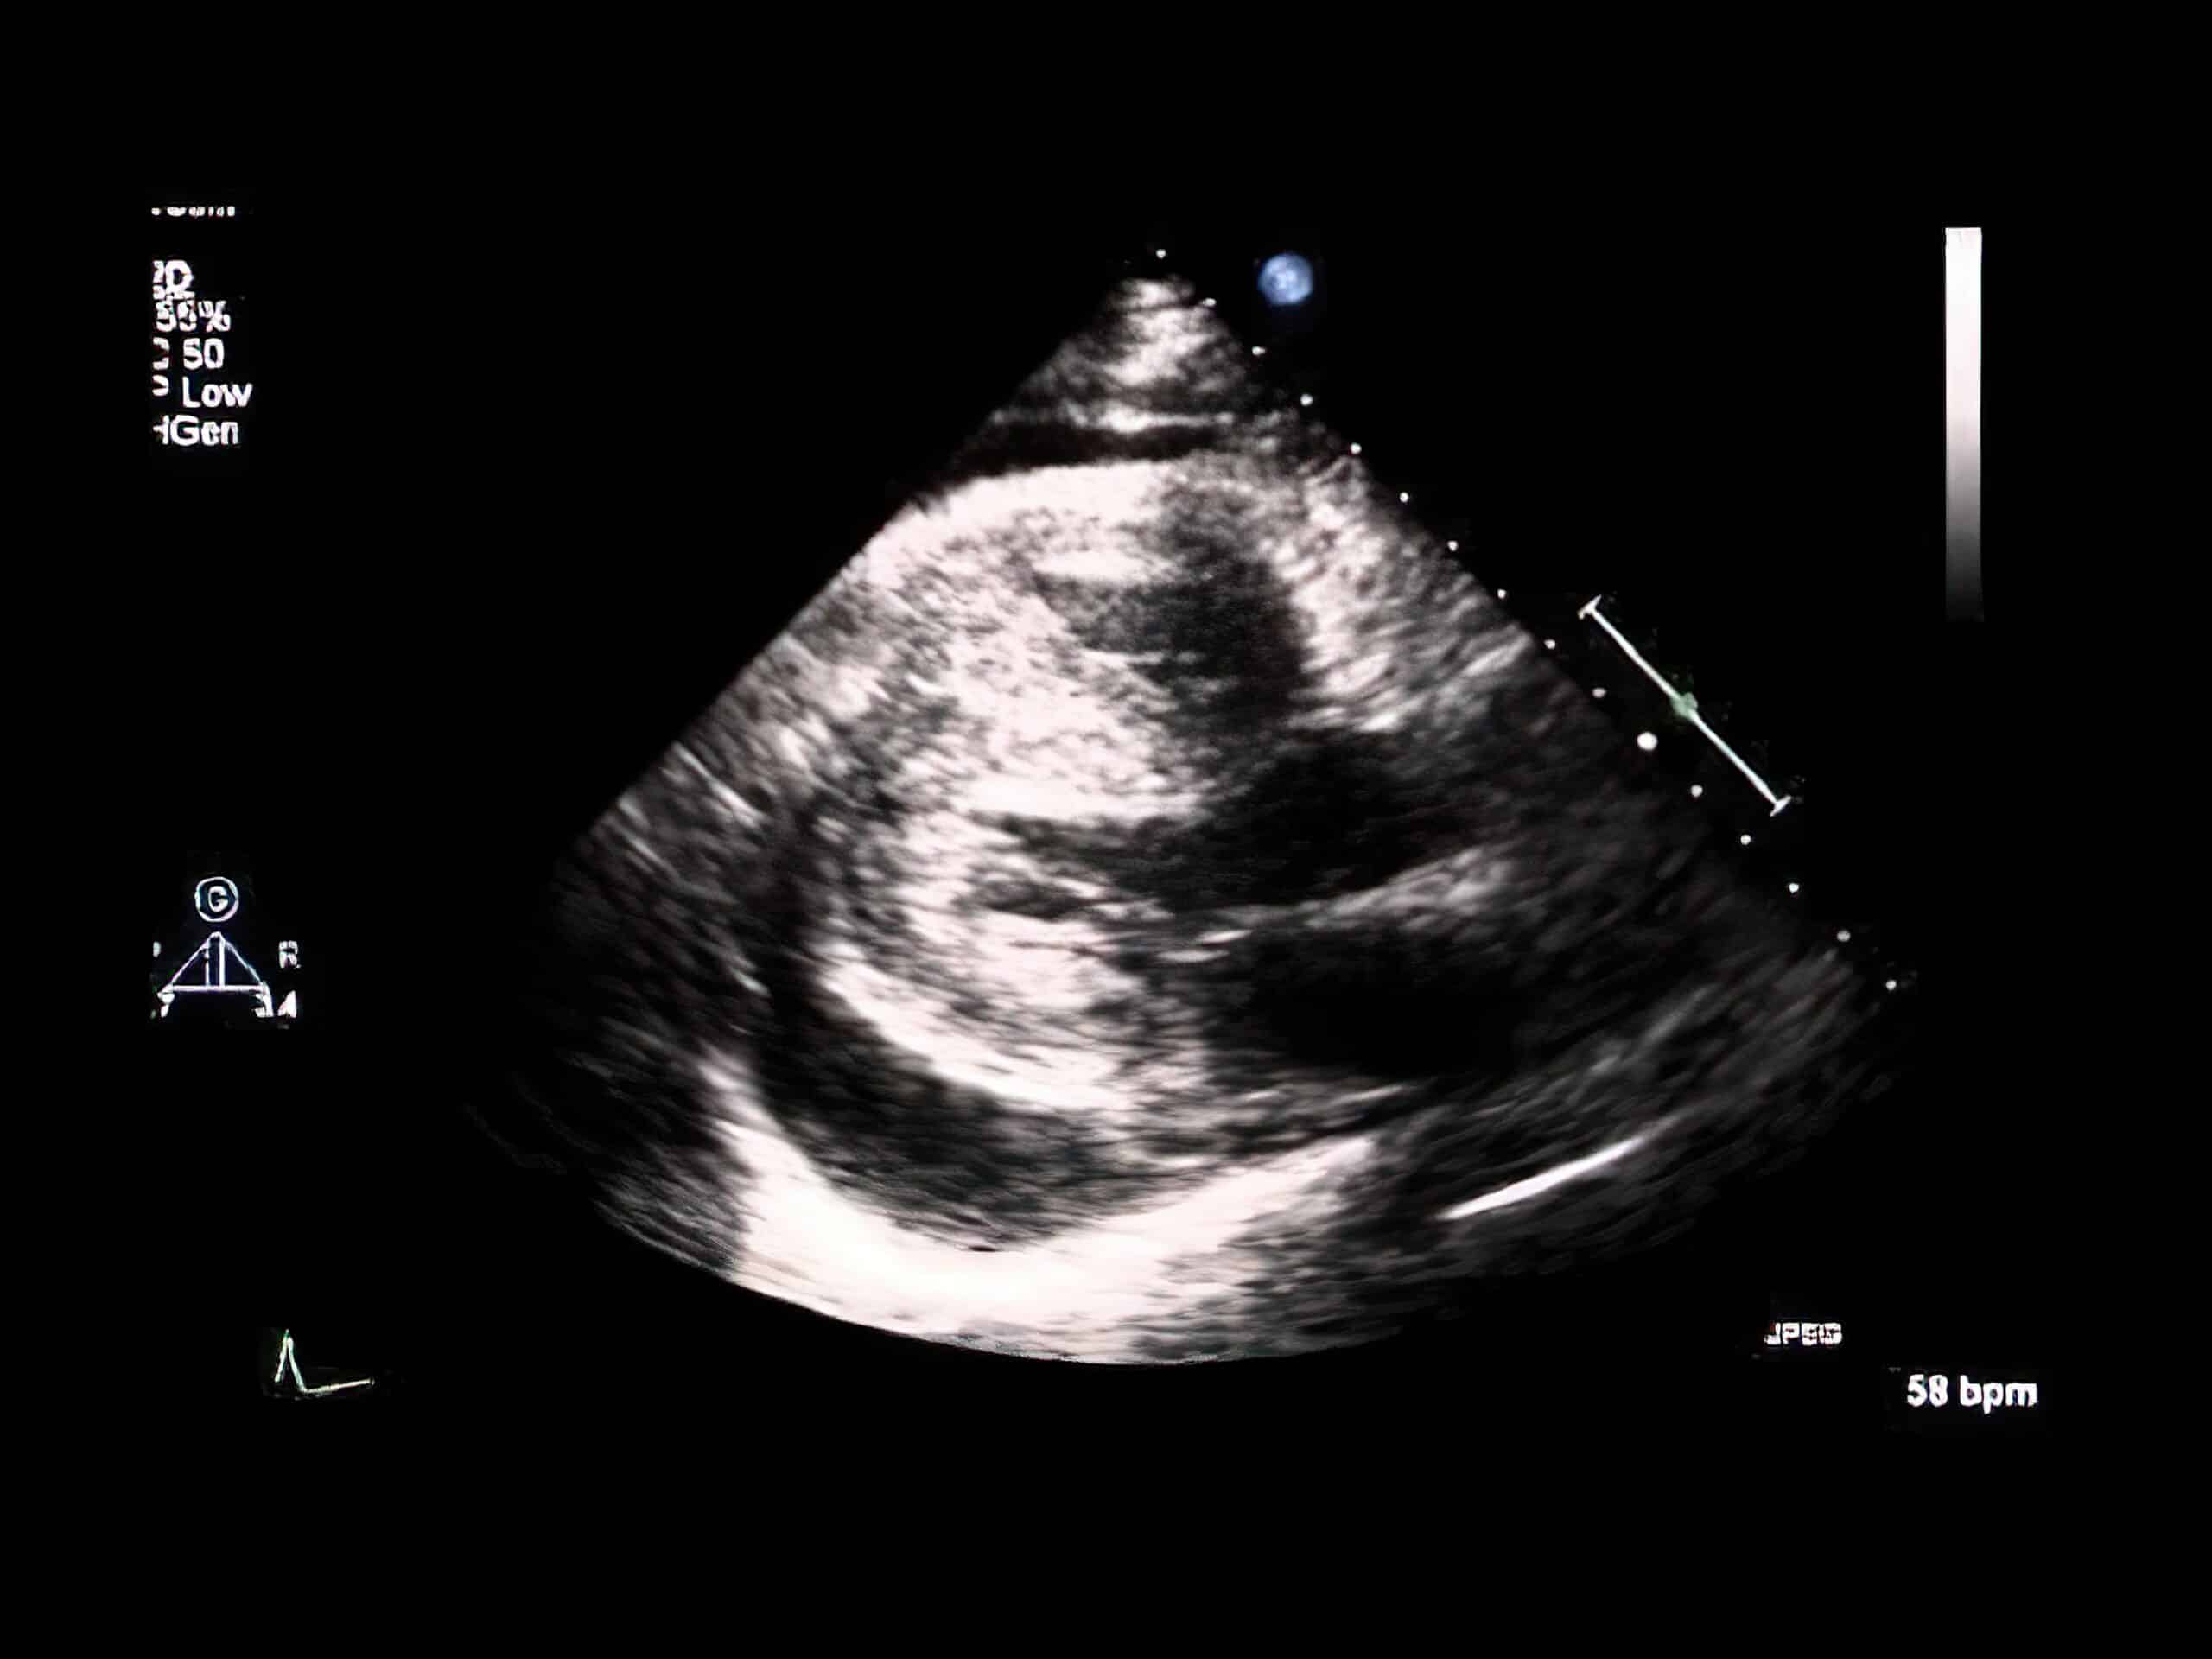

Biventricular Hypertrophy Echocardiogram